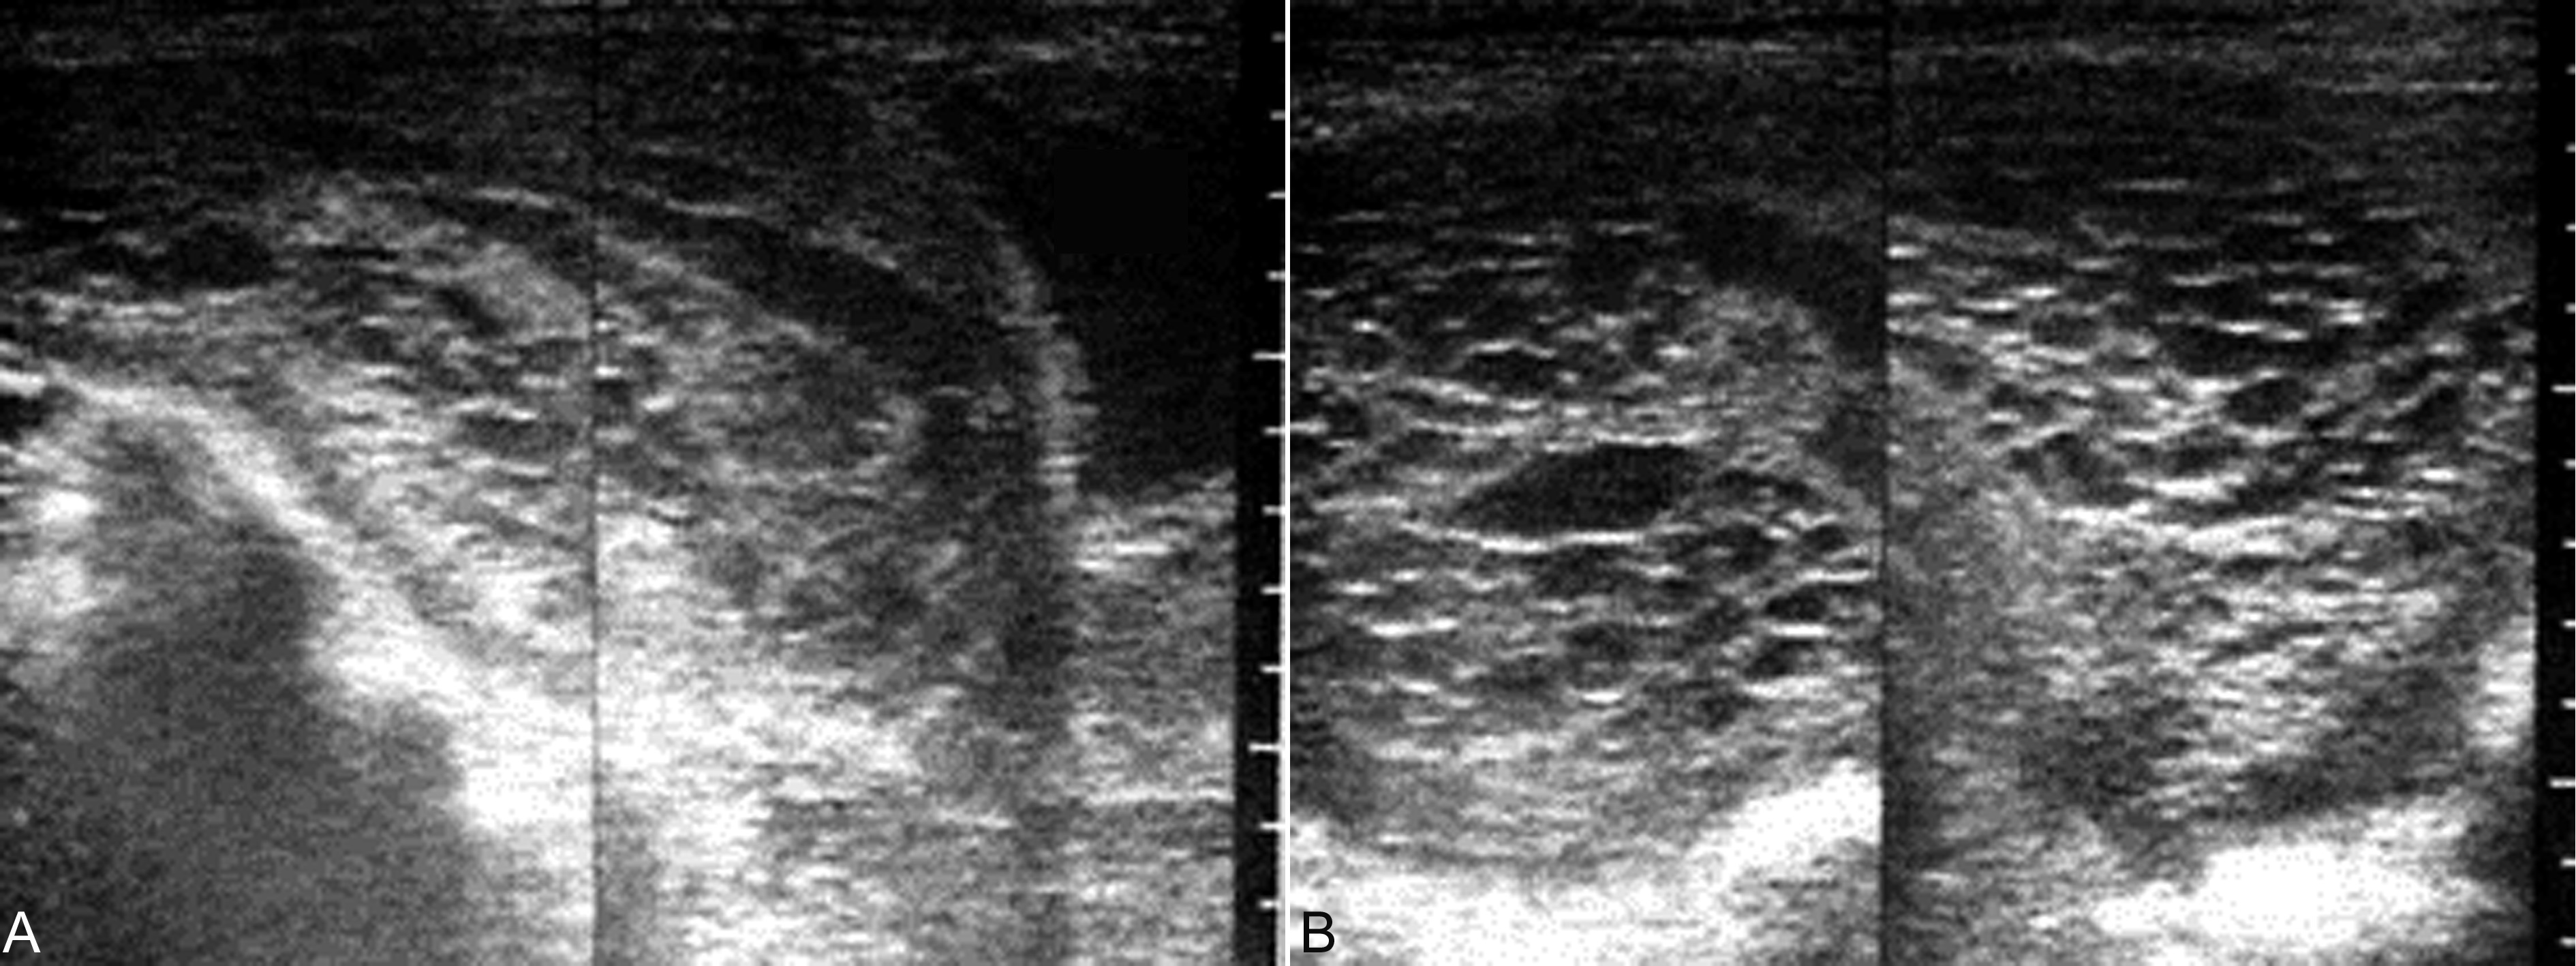

1.完全型葡萄胎 子宫明显大于停经月份,增长迅速,子宫壁较薄,完整;宫腔内显示囊状或蜂窝状回声,形如葡萄,大小不等,排列不规律(图1)。早期仪器分辨率低、灰阶较少时多显示为“落雪状”回声,而现代的高分辨率的仪器均可显示典型的声像图改变。在宫腔内水泡状回声的中间,可见由宫腔内出血、积聚形成的不规则无回声区;胎儿及其附属物,包块胎盘、脐带等均不能显示。一侧或双侧附件区可显示单房性或多房性无回声区,提示有黄素囊肿形成(见图2,图3)。

超声显像检查时,葡萄胎表现的声像图特点与滋养细胞的增生活跃程度和水泡样变的程度有一定关系。滋养细胞水泡样变越明显在声像图上显示的回声就越典型、水泡也多比较大(图1);滋养细胞增生越活跃、水泡样变越不典型,在声像图上显示的水泡就越小、越不典型(图3)。临床观察资料表明,前者的临床经过要明显地好于后者。

图1葡萄胎声像图